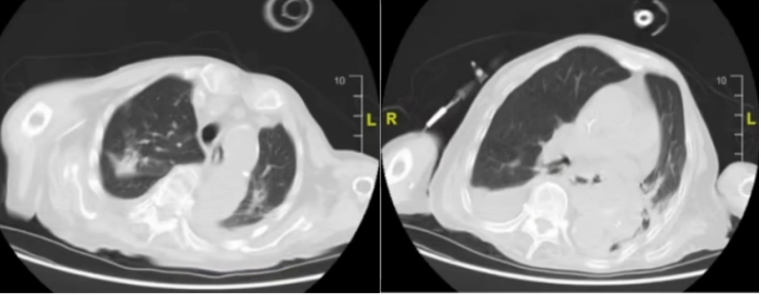

• 胸部CT:可见渗出性改变,部分区域有实变影,胸腔积液右侧为主)(图1)

1  患者入院胸部CT(2024-04-11)

423日复查胸部CT:肺部病灶较前无明显变化(图5)

5  复查胸部CT(2024-04-23)